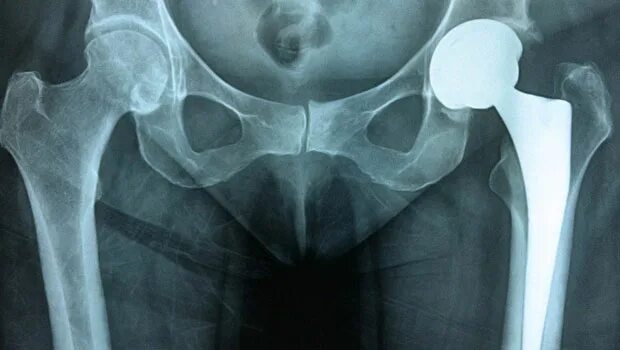

Очередь на протезирование тазобедренного сустава